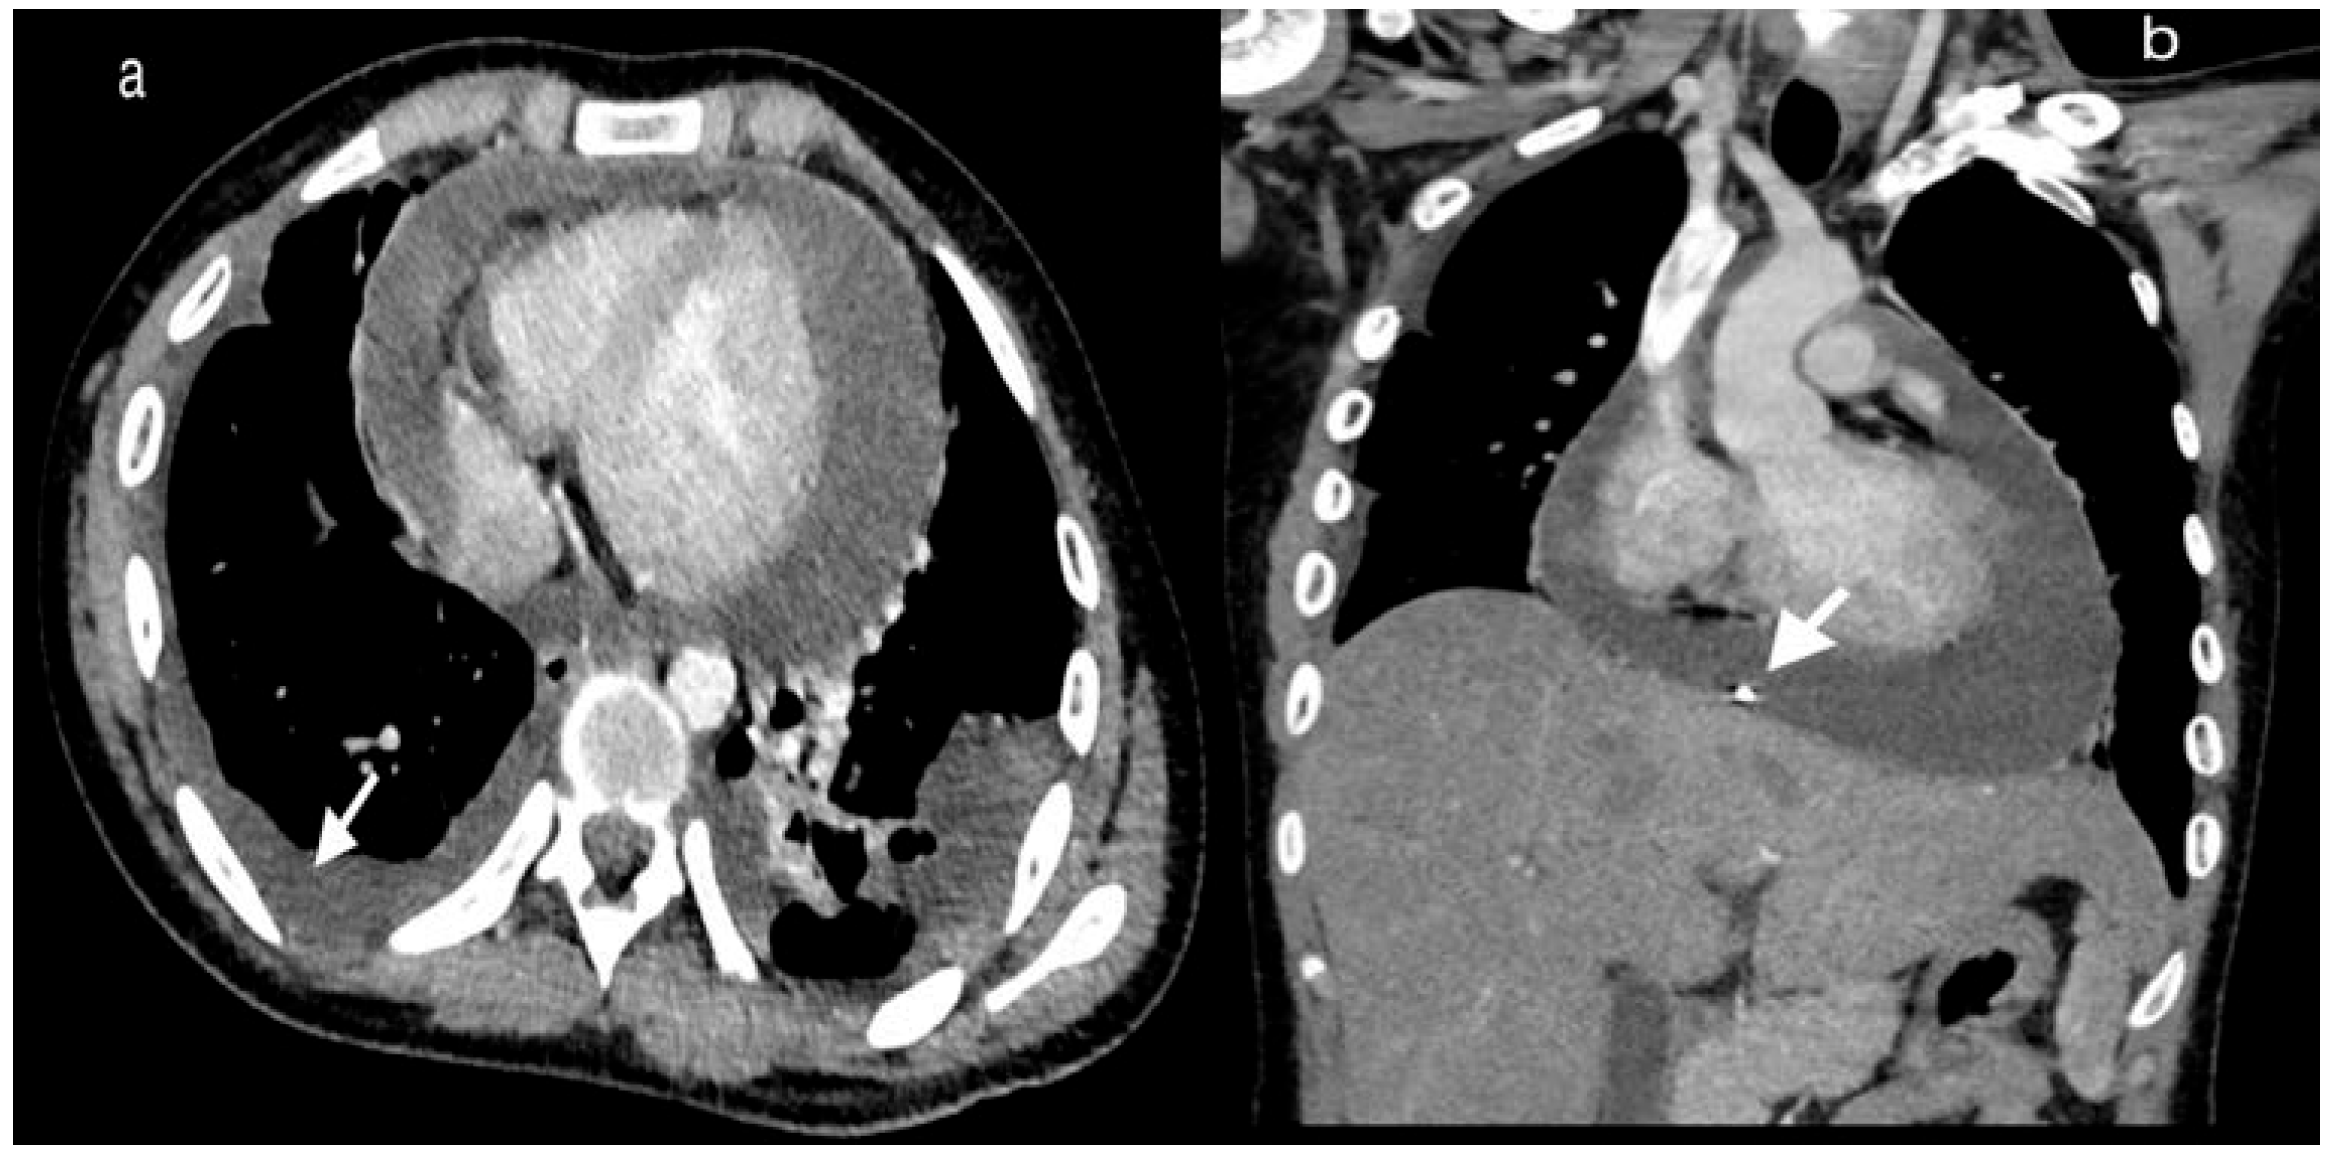

Case report